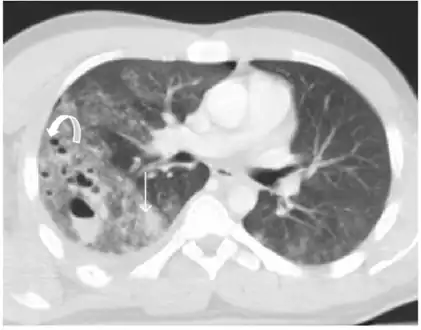

Pulmonary lacerations- Multiple focus of pulmonary lacerations can be depicted, some of them are filled with air, others filled with blood, and some filled with both, making an air-liquid level -

Pulmonary laceration may not be visible using chest X-ray because an associated pulmonary contusion or hemorrhage may mask it.[1][9] As the lung contusion clears (usually within two to four days), lacerations begin to become visible on chest X-ray.[3] CT scanning is more sensitive and better at detecting pulmonary laceration than X-rays are,[1][5][12][15] and often reveals multiple lacerations in cases where chest X-ray showed only a contusion.[12] Before CT scanning was widely available, pulmonary laceration was considered unusual because it was not common to find with X-ray alone.[12] On a CT scan, pulmonary lacerations show up in a contused area of the lung,[9] typically appearing as cavities filled with air or fluid[16] that usually have a round or ovoid shape due to the lung's elasticity.[4]

Hematomas appear on chest radiographs as smooth masses that are round or ovoid in shape.[1] Like lacerations, hematomas may initially be hidden on X-ray by lung contusions, but they become more apparent as the contusion begins to heal.[1] Pneumatoceles have a similar shape to that of hematomas but have thin, smooth walls.[17] Lacerations may be filled completely with blood, completely with air, or partially with both.[4] Lacerations filled with both blood and air display a distinctive air-fluid level.[4] A single laceration may occur by itself, or many may be present, creating an appearance like Swiss cheese in the radiography of the lung.[4]